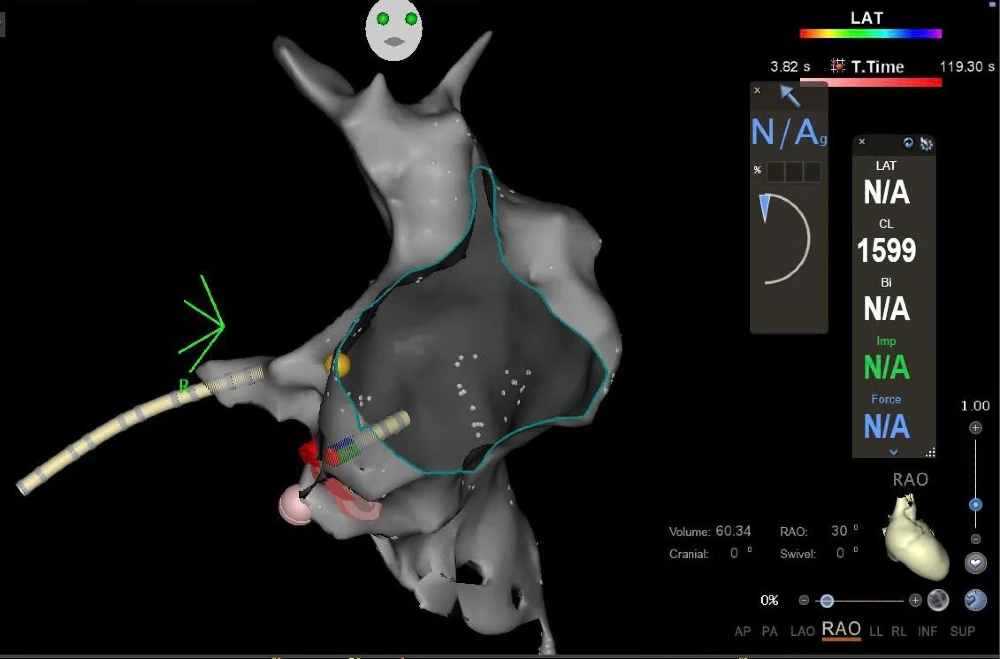

Các catheter xoang vành và các buồng tim được dựng hình lại như hình vẽ, và tiến hành tìm đường dẫn truyền phụ bằng kinh nghiệm suy luận giải phẫu tim và không gian 3D.

Tại vị trí thành sau của vòng van 3 lá chúng tôi ghi nhận điện thế bất thường của đường dẫn truyền phụ. Tiến hành cắt đốt vị trí này chấm dứt hoàn toàn đường dẫn truyền phụ và bệnh nhân không còn những cơn nhịp nhanh bất thường nguy hiểm.

Hệ thống mapping 3D Carto giúp dựng hình buồng tim và xác định nhanh vị trí ổ loạn nhịp ở thành giữa vách buồng tống thất (P). Đặc biệt hơn, chúng tôi đưa vào sử dụng catheter cắt đốt có cảm biến lực (Smart touch) là một trong những catheter cắt đốt tiên tiến nhất hiện nay.

Cụ thể, cảm biến lực trên đầu catheter sẽ biểu thị lực áp của catheter trong buồng tim cũng như các hướng xoay được biểu thị màu và mũi tên được biểu hiện liên tục lên màn hình giúp cho các bác sĩ di chuyển catheter và điều chỉnh độ áp được dễ dàng.